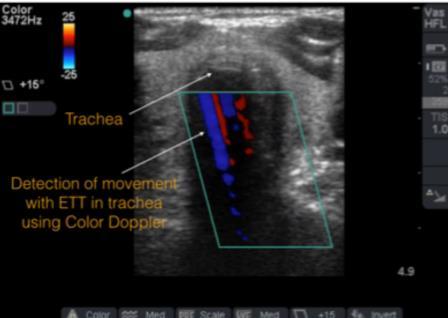

Tips and Tricks:Airway Ultrasound

American College of Emergency Physicians

ACEP Emergency Ultrasound section.

DOI: https://www.acep.org/how-we-serve/sections/emergencyultrasound/news/june-2015/tips-and-tricks-airway-ultrasound/.

Alice Chao, MD, Laleh Gharahbaghian, MD.

Excerpt

In recent years, the use of ultrasound (US) for confirmation of endotracheal tube (ETT) placement has gained increasing popularity. Several techniques already exist to confirm endotracheal tube placement. However, every tool has its limitations, and some are not always available in the emergency department (ED). The likely reason that airway US has gained attention is the ease at which images can be obtained. Airway US for ETT confirmation is best used when the end-tidal CO2 monitor is not accurate, radiology is unavailable, the patient arrives intubated and requires airway confirmation, or the patient does not respond as expected after intubation. There are some tips and tricks that can assist in obtaining the best view.